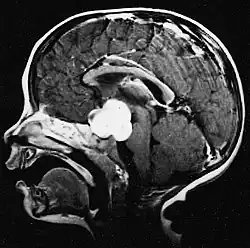

Pilocytic astrocytoma (and its variant pilomyxoid astrocytoma) is a brain tumor that occurs most commonly in children and young adults (in the first 20 years of life). They usually arise in the cerebellum, near the brainstem, in the hypothalamic region, or the optic chiasm, but they may occur in any area where astrocytes are present, including the cerebral hemispheres and the spinal cord. These tumors are usually slow growing and benign, corresponding to WHO malignancy grade 1.[1]

Pilocytic astrocytomas are often cystic tumors, and, if solid, tend to be well-circumscribed.

Under the microscope, the tumor is seen to be composed of bipolar cells with long "hair-like" GFAP-positive processes, giving the designation "pilocytic" (that is, made up of cells that look like fibers when viewed under a microscope[6]). Some pilocytic astrocytomas may be more fibrillary and dense in composition. The presence of Rosenthal fibers,[7] eosinophilic granular bodies, and microcysts can often be seen. Myxoid foci and oligodendroglioma-like cells may also be present, though these are not specific to pilocytic astrocytoma. Long-standing lesions may show hemosiderin-laden macrophages and calcifications.